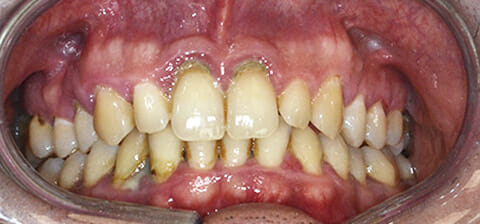

Paziente di 38 anni affetto parodontite aggressiva generalizzata.

Il paziente presentava una grossa quantità di tartaro ematico, suppurazione nella maggior parte dei siti e mobilità di diversi elementi dentali.